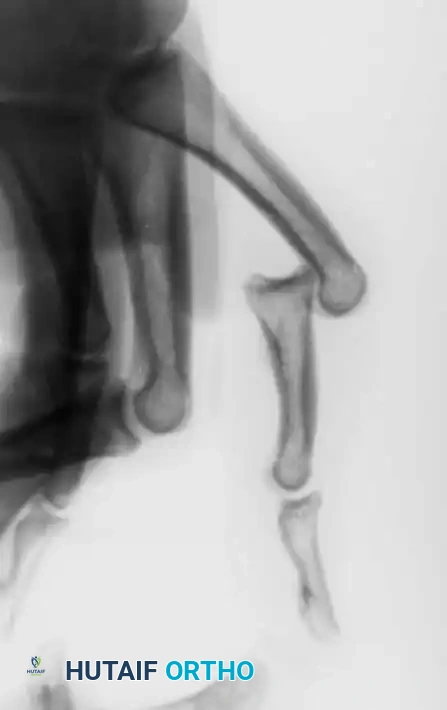

Management of Severe Comminution

Open or severely comminuted fractures of the phalanges may be unsuitable for internal fixation using traditional plates or screws, as the hardware may further fragment the bone or require excessive soft-tissue stripping.

In such cases, external fixation using a mini external fixator is ideal. Alternatively, the technique suggested by Milford utilizes percutaneous transverse K-wires joined externally by a segment of polymethyl methacrylate (PMMA) bone cement. This acts as a custom, low-profile external fixator. Final alignment of the bone is manually maintained while the acrylic cement sets.